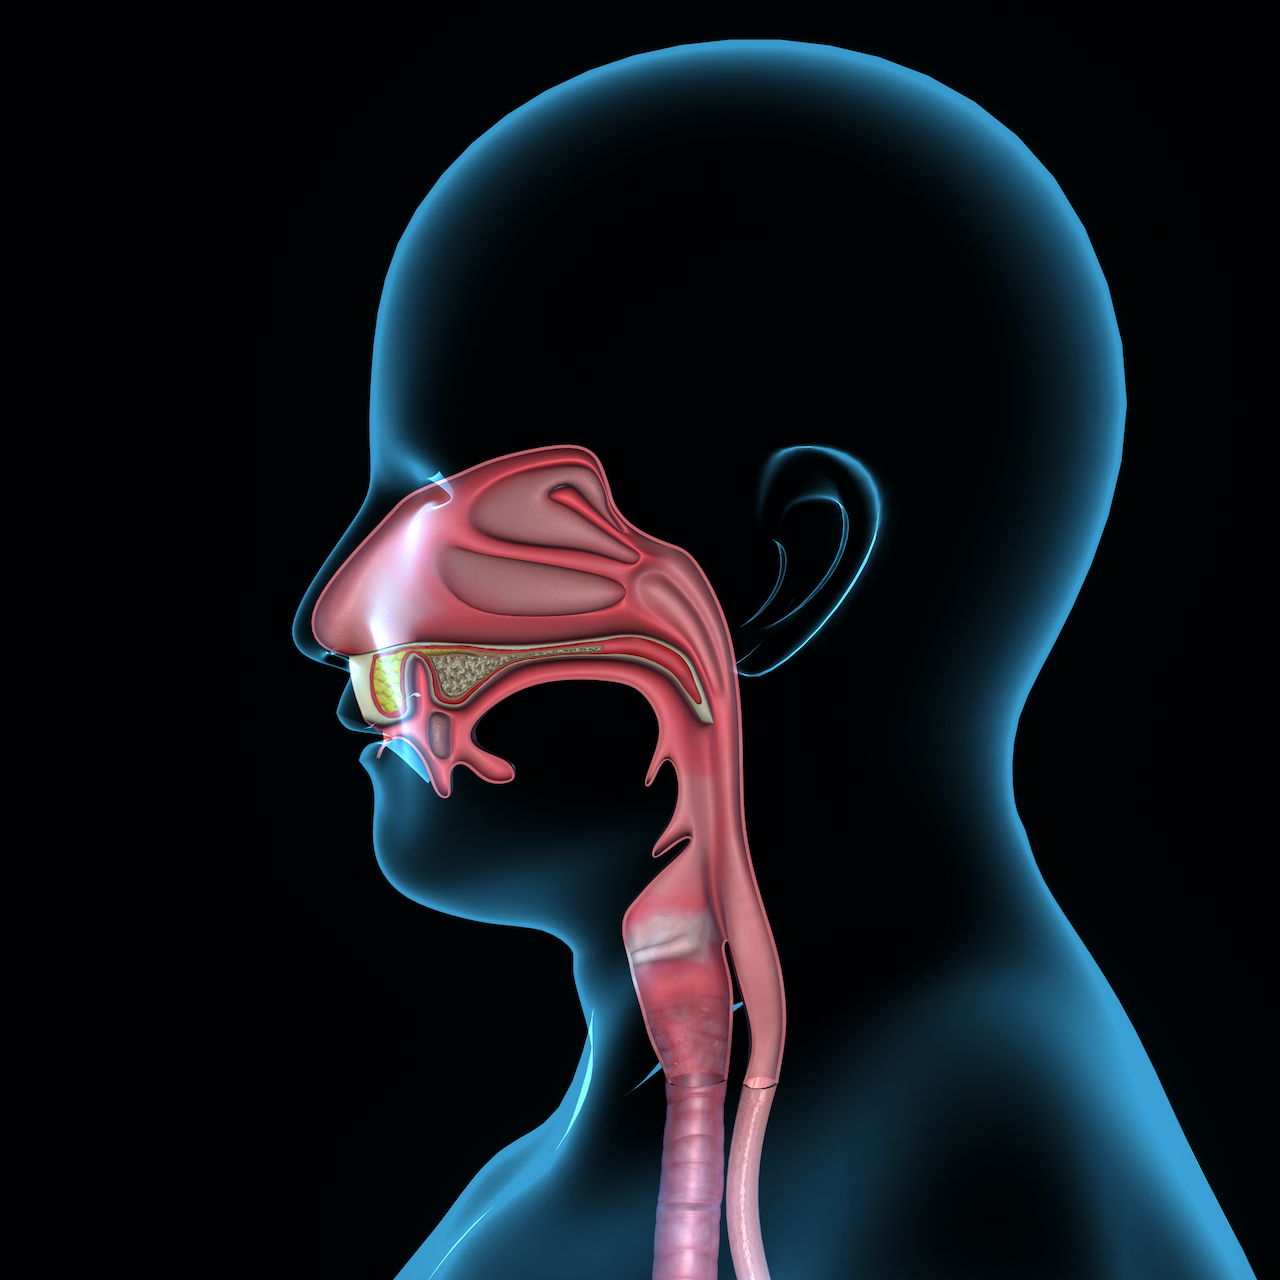

Especialização em Disfagias Orofaríngeas - edição 2025/26

- Imagem principal

- DataInício a 15 de Fevereiro de 2025 Carga Horária: 240 horas